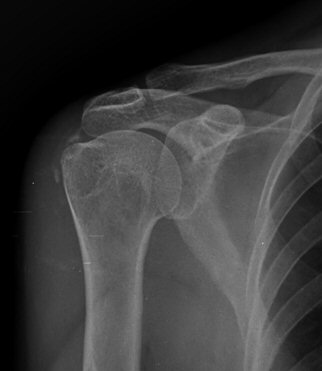

ÃÊÀ½ÆÄ °Ë»ç

À̵ιڱ٠Ⱦ´Ü¸é°Ë»ç¿¡¼­ Á¡¾×³¶³» °í¿¡ÄÚ ¼®È¸È­ À½¿µµéÀÌ °üÂûµÊ(±×¸² 1, 2, 5)

´Ü¼ø¹æ»ç¼±°Ë»ç

¼®È¸È­ À½¿µÀÌ °üÂû µÊ(±×¸² 9, 10)